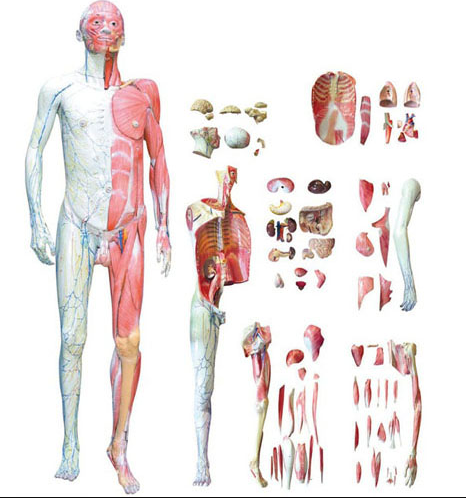

功能特點:

■ 尺(chǐ)寸(cùn):自(zì)然尺寸的1/2;

■ 部件:1部件,固定在底座上;

■ 功能:浮(fú)雕模型展(zhǎn)示了人類周圍和中(zhōng)樞神經係統的概貌:頭部是(shì)開放的,露出大腦和小腦;主要神經的通路與骨骼有關;

■ 材質:進口環(huán)保PVC材料(liào),進口環保油漆;